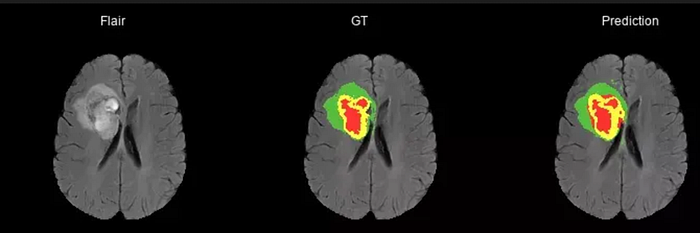

1. Brain Tumor Detection using image segmentation

Brain tumor detection is one of the important projects for those students who are interested in machine and deep learning. The detection of the brain tumor at a very early stage is a very difficult task for doctors trying to find the tumor through MRI images but the images are more prone to noises and environmental interferences. Hence there came the need to develop a system to detect the brain tumor using images.

The process is straightforward. In this, the image is converted into a grayscale image. The images are applied filters to remove the noise and other interferences. The system generates the image processing steps that are applied to the images the user selects. The algorithm is applied to the image to detect the brain tumor. Image segmentation is applied to the image to get the edges of the image with proper accuracy. The only disadvantage of this project is that it works on MRI images.

The implementation of this project would be able to save many people’s lives as its application of allowing to detection of the tumor at the early stages will help the doctors help save the patient by giving the appropriate treatment.